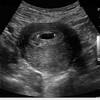

–Highest incidence at 4 to 5 years

–Highest incidence in males (1.6 males:1 females)

Sonographic appearance